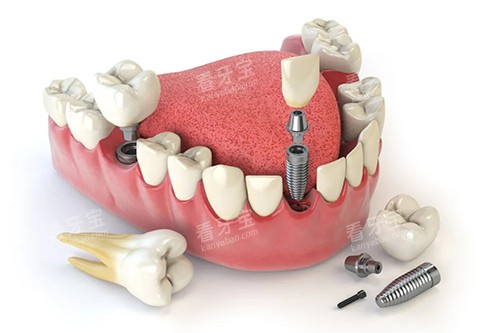

他们不仅在牙齿矫正、牙齿种植、口腔修复等常见口腔项目上技术娴熟,还在一些复杂的口腔疾病治疗方面有着独特的见解和治疗方法。

例如,在牙齿种植领域,医生们能够根据患者的口腔情况和身体状况,制定个性化的种植方案,确保种植结果的稳定性和美观性。